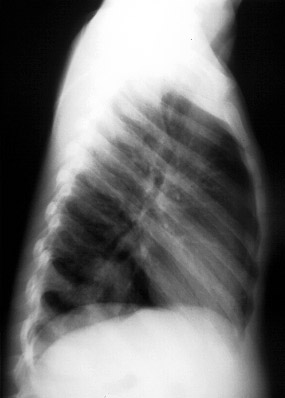

Key takeaway: In febrile children with a benign abdominal exam, right lower-lobe pneumonia is a classic cause of RUQ abdominal pain—obtain a chest radiograph when suspected.

This child presented with complaints of fever and RUQ abdominal pain. The abdominal exam was benign. What's causing the upper abdominal pain?

This high-miss item tests recognition that lower-lobe pneumonia can present with abdominal pain, particularly RUQ pain, in children due to diaphragmatic irritation and shared innervation. A benign abdominal exam with fever should prompt consideration of chest pathology, and CXR often reveals a basilar infiltrate.

The keyed answer (pneumonia) is correct and guideline-concordant. ACR Appropriateness Criteria (2023) for suspected appendicitis in children explicitly notes pneumonia as an extra-abdominal cause of abdominal pain and supports chest imaging when clinical features suggest it. AAP Pediatrics in Review (2021) likewise emphasizes lower-lobe pneumonia as a common mimic of acute abdomen in pediatrics.

| pneumonia | Recognition of extra-abdominal cause of abdominal pain | Correct: Lower-lobe pneumonia commonly causes RUQ pain in children; CXR shows basilar infiltrate. |

In a febrile child with RUQ or right lower quadrant pain and a benign abdominal exam, always consider and image for right lower-lobe pneumonia.